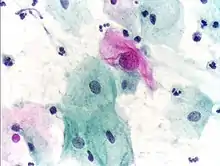

Cytopathology: microscopic appearance of a Pap test. The pink cell at the center with a large nucleus is abnormal, compatible with low-grade dysplasia.

• Cytopathology – the examination of loose cells spread and stained on glass slides using cytology techniques

Cytopathology

Cytopathology is a sub-discipline of anatomical pathology concerned with the microscopic examination of whole, individual cells obtained from exfoliation or fine-needle aspirates. Cytopathologists are trained to perform fine-needle aspirates of superficially located organs, masses, or cysts and are often able to render an immediate diagnosis in the presence of the patient and consulting physician. In the case of screening tests such as the Papanicolaou smear, non-physician cytotechnologists are often employed to perform initial reviews, with only positive or uncertain cases examined by the pathologist. Cytopathology is a board-certifiable subspecialty in the U.S.